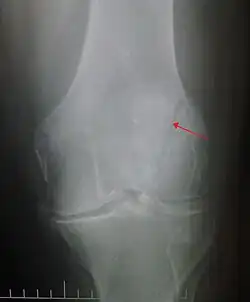

Some people have a normal bipartite patella or two-part patella which can appear as a fracture. The fragment is usually seen in the top outer corner of the patella and can be distinguished from a fracture by being present in both knees.[6]